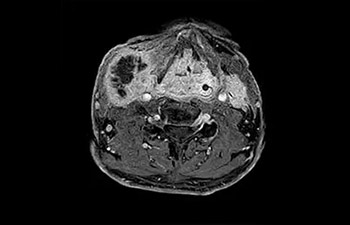

En una sociedad en la que los reembolsos son cada vez menos cuantiosos y las enfermedades crónicas se traducen en un aumento de los procedimientos de RM y en tiempos de espera más largos, los servicios de radiología se ven sometidos a una presión cada vez mayor. La aceleración pone en riesgo la calidad de la imagen o bien se puede aplicar a todo el espectro de las exploraciones rutinarias. Por lo tanto, para satisfacer la creciente demanda de productividad, todavía es necesario dar un paso adelante más en cuanto a la aceleración. Aprovechando nuestra dilatada posición de liderazgo en el ámbito de la velocidad (de la mano de SENSE), Philips presenta Compressed SENSE, un avance en términos de productividad.

• Es una innovadora técnica de aceleración que no solo permite agilizar las secuencias, sino todo el estudio. • Implementación especial con la que las exploraciones en 2D y 3D pueden llegar a ser hasta un 50% más rápidas con una calidad de imagen prácticamente equivalente.1

• Se puede usar con todos los contrastes y con todas las regiones anatomías.